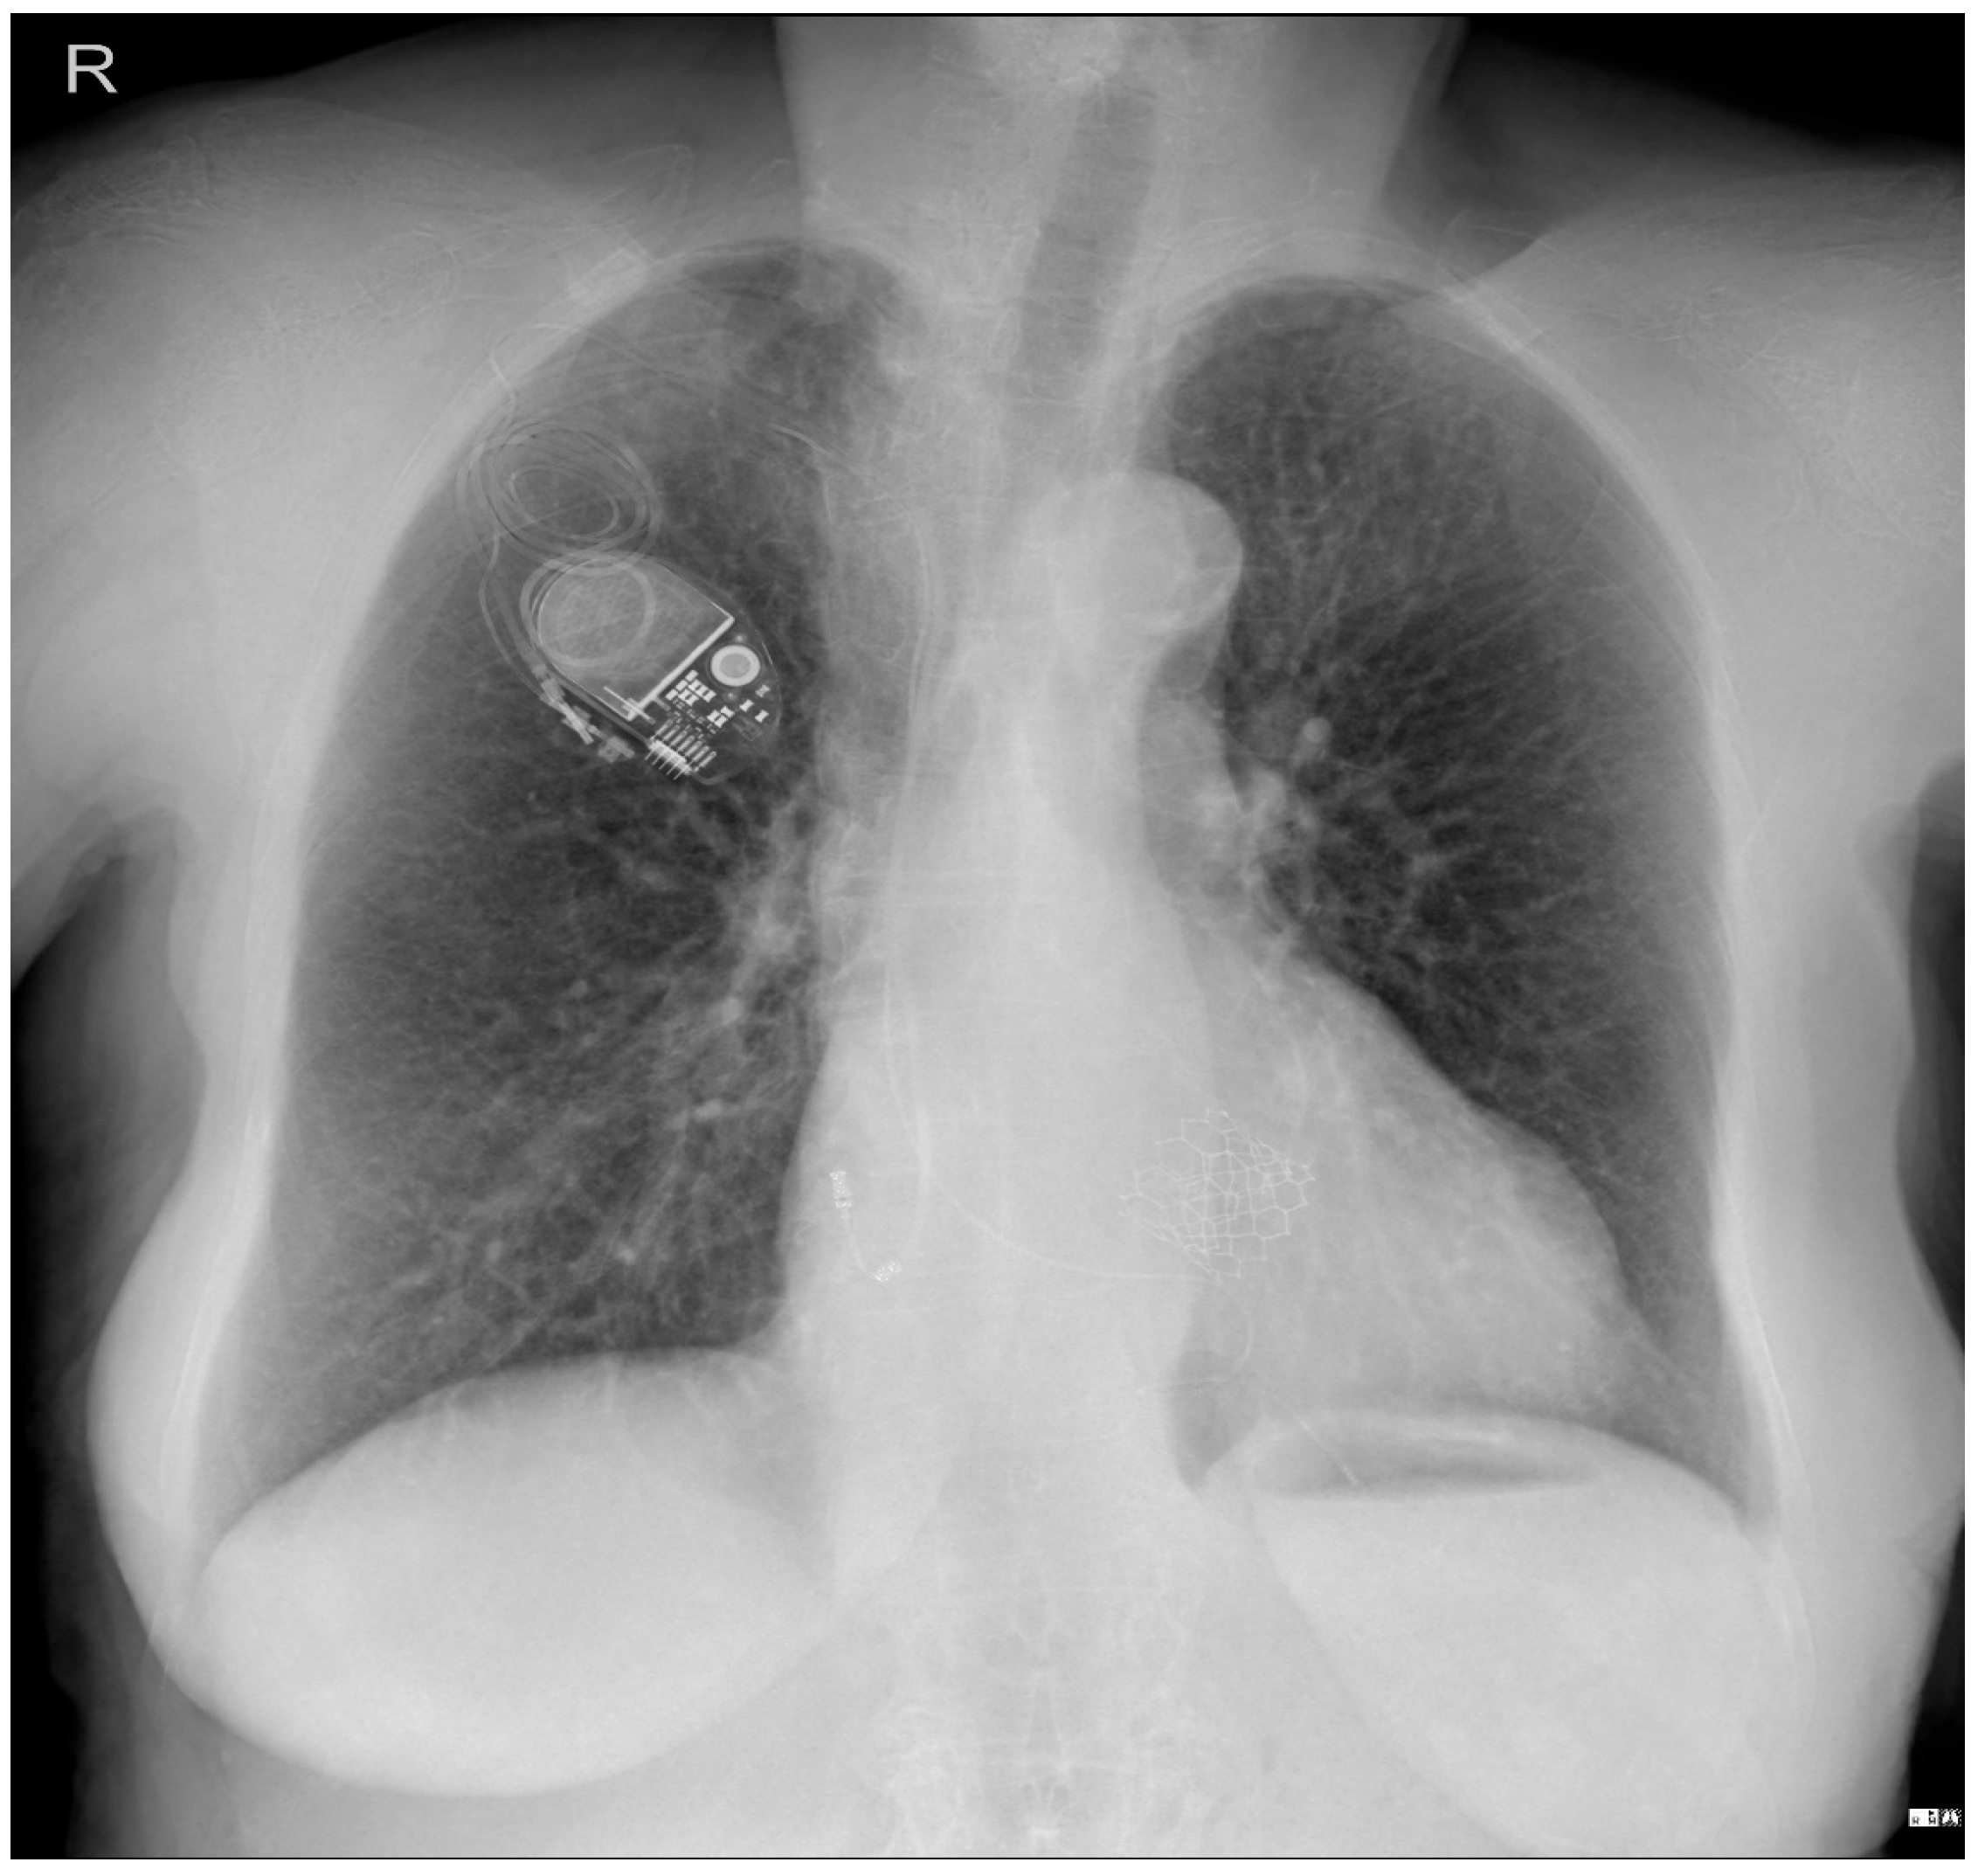

To investigate a potential cause of malfunction of the intracardiac device, it was decided that both a chest X-ray (Figure 2) and an echocardiogram (Figure 3) would be performed. These diagnostic tests were selected to confirm or rule out the possibility of a pacing probe fracture, particularly considering the patient’s recent fall, which may have compromised the integrity of the device or the intracardiac pacing leads. The chest X-ray assesses the device positioning and identifies potential fractures of the pacing leads. Concurrently, the echocardiogram provides critical information regarding cardiac function and its interaction with the implanted device. Together, these diagnostic modalities are essential for optimal management of the patient.

Figure 3. Echocardiography exam images at admission: A transthoracic echocardiography (TTE) exam was performed in the apical 4-chamber view (a,b) and subcostal view (c,d), revealing the insertion of the pacing probe into the myocardium of the right ventricle free wall, without any visible fractures or ruptures of the lead.

Figure 7. Holter ECG strip: The ventricular stimulated rhythm has a rate of 70 bpm. The pacemaker-generated spike is followed by a wide QRS complex. The lead is placed at the apex of the right ventricle (see Figure 3 and Figure 13C), depolarizing the right ventricle before the left ventricle. The lead is in contact with the myocardium, and the conduction is slow, cell-to-cell, thus generating a broad QRS, reflecting the interventricular and intraventricular dyssynchrony.